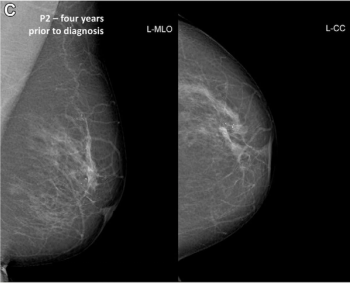

Artificial intelligence (AI) software assigned high malignancy risk scores to mammography exams completed up to two years prior to breast cancer diagnosis in over 38 percent of screen-detected cancer cases and over 39 percent of interval cancer cases, according to newly published research.